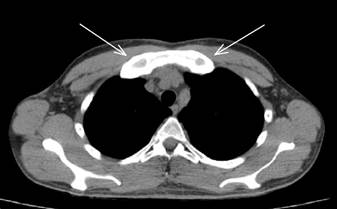

КТ органов грудной полости от 02.07.2024г.: картина облитерации синхондроза между рукояткой и телом грудины, гиперостоза грудино-реберного сочленения, на уровне рукоятки грудины и оссифицированных хрящевых отделов первых ребер с формированием костного блока, с признаками частичного сращения Th 3-4 позвонков и формированием костного блока (нельзя исключить проявление системного аутоиммунного воспалительного процесса), очагово-инфильтративных изменений в легких, органах средостения не получено (рис. 1).

Рис.1. Компьютерная томография органов грудной полости: гиперостоз грудино-реберного сочленения на уровне рукоятки грудины и оссифицированных хрящевых отделов первых ребер с обеих сторон (оригинальные данные компьютерной томографии, выполненной в одной из частных клиник города)

Длительное амбулаторное наблюдение у непрофильного специалиста и симптоматическое лечение пациента с 2014 года привели к развитию необратимых последствий остеита: облитерация синхондроза между рукояткой и телом грудины, гиперостоз грудино-реберного сочленения, на уровне рукоятки грудины и оссифицированных хрящевых отделов первых ребер, с формированием костного блока, с признаками частичного сращения Th 3-4 позвонков и формированием костного блока, и значительному снижению качества жизни пациента.